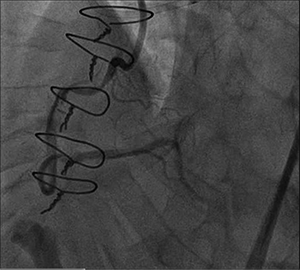

In the interim, the patient reported improvement in his symptoms. He returned 2 months after the initial procedure for follow-up angiography, which revealed that the subintimal space remained open (figure 2). Antegrade wiring then progressed to the distal RCA and, subsequently, stenting was performed (figure 3).

Figure 2. Angiography 2 months after initial balloon angioplasty